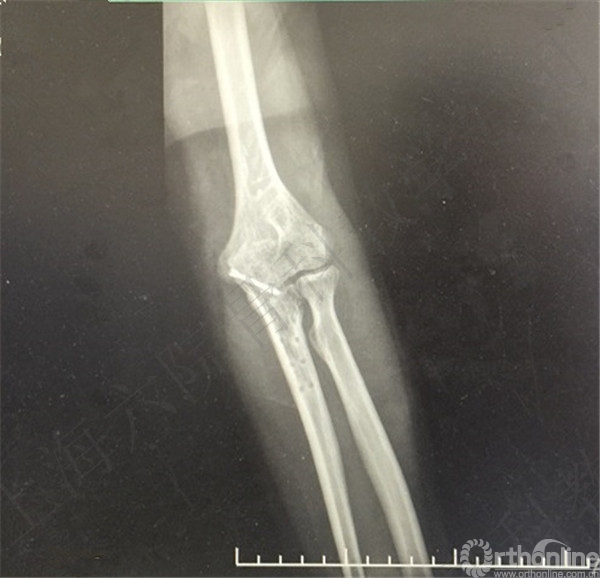

患者左尺骨鹰嘴骨折,取出内固定。

术后X线摄片示:左尺骨鹰嘴内固定取出,空心钉留置。

医方在术前未充分告知患者存在内固定取出困难、断钉、留置内固定、术中骨折和术后在骨折等风险。医方存在告知缺陷等过失。